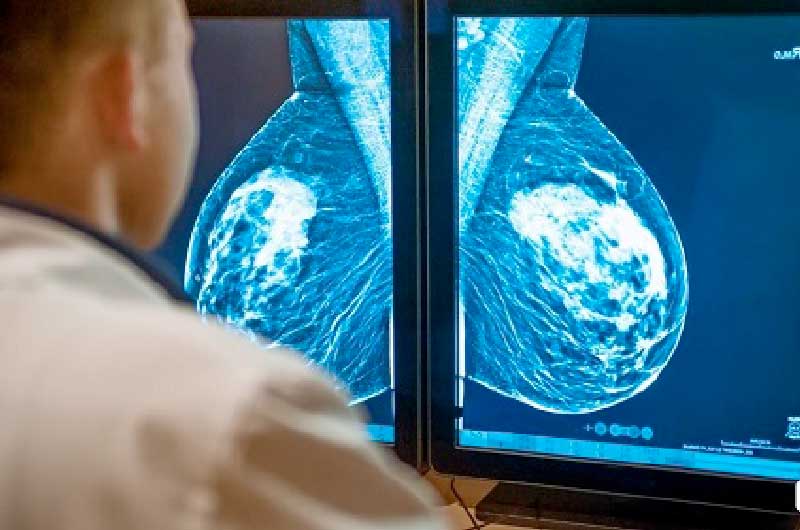

De autoria do deputado Adjuto Afonso (PDT), tramita na Assembleia Legislativa do Amazonas (Aleam), o Projeto de Lei nº 05/2022, que visa ampliar o direito à mamografia gratuita na rede de saúde pública do Amazonas para mulheres a partir dos 40 anos de idade, em adequação à Lei Federal nº 11.664/2008. O parlamentar teve por base o número de mulheres acometidas por câncer de mama no país, que já ultrapassou os 66 mil, segundo o Instituto Nacional de Câncer (Inca).

O PL determina que o exame seja realizado anualmente e tem o objetivo de ampliar do uso da mamografia no que se refere ao rastreamento do câncer de mama em mulheres assintomáticas com risco habitual, sem necessidade de recomendação médica a partir dos 40 anos.

Também fica estabelecido o direito à realização, segundo avaliação do médico assistente, de ultrassonografia mamária para mulheres jovens com elevado risco de câncer de mama ou que não possam ser expostas a radiação e para quem está na faixa etária de 40 a 49 anos de idade ou com alta densidade mamária.